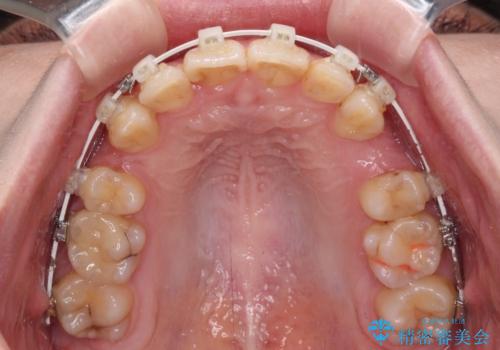

- 前歯のデコボコを気にして来院された患者様です。

上下の前歯にデコボコがあり、更にはディープバイトにより下顎前歯の大半が隠れている状態でした。

上顎左右第一小臼歯の2本を抜歯し、ワイヤー装置を使用して咬み合わせ高さを改善しながら、歯列を整えて行くこととしました。

事前にむし歯の疑いがある歯があり、処置を行いましたが、矯正治療中に失活してしまい、ワイヤー装置除去後に、根管治療とセラミッククラウンによる補綴治療を行いました。

矯正治療は2年半ほで無事におけることができました。